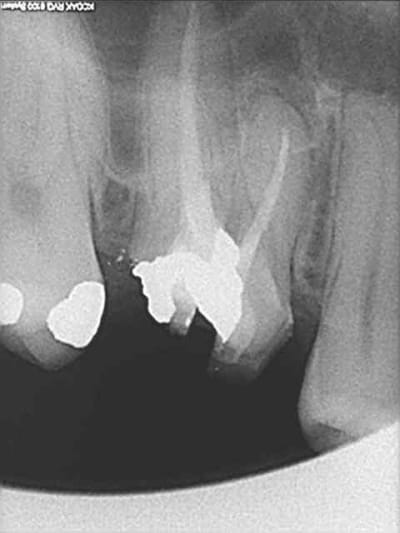

en ce qui concerne la planification j'ai une 3D kodak je me sert des cotes de l'implant Alphatech qui bien que n'ayant pas la même forme, a les mêmes dimensions.

Gar cross section1 tgeo1t - Eugenol

Gar cross section2 aw0gxu - Eugenol

Garaxial1 az74ic - Eugenol

Gart axial2 veeu9c - Eugenol

Gart panoramic1 ssmlda - Eugenol

Gart panoramic2 isuhmz - Eugenol

100 5820 cjhkpn - Eugenol

100 5933 zykp1c - Eugenol